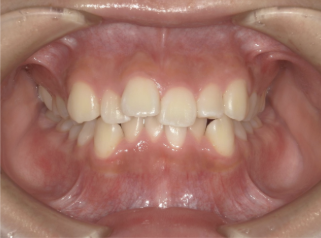

中等度叢生・八重歯症例画像

中等度(しっかり重なりがわかる)の方の場合

前歯だけでなく奥歯にも重なりがはっきり見え、磨きにくい場所が多かったり、虫歯や歯周病のリスクが気になり始める段階です。

見た目のガタつきだけでなく、日常のケアにも影響が出やすい状態といえます。 このレベルになると、非抜歯で歯列を広げて並べる方法と、抜歯して十分なスペースを作り、かみ合わせと口元のバランスも整える方法の両方が検討されます。

どちらが最適かは歯と顎のバランスによって異なりますが、治療期間の目安は1年〜1年半ほど。デコボコとかみ合わせをしっかり整えながら進めるケースが多くなります。